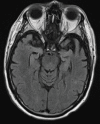

Neurodegenerative diseases are a devastating group of disorders that can be difficult to accurately diagnose. Although these disorders are difficult to manage owing to relatively limited treatment options, an early and correct diagnosis can help with managing symptoms and coping with the later stages of these disease processes. Both anatomic structural imaging and physiologic molecular imaging have evolved to a state in which these neurodegenerative processes can be identified relatively early with high accuracy. To determine the underlying disease, the radiologist should understand the different distributions and pathophysiologic processes involved. High-spatial-resolution MRI allows detection of subtle morphologic changes, as well as potential complications and alternate diagnoses, while molecular imaging allows visualization of altered function or abnormal increased or decreased concentration of disease-specific markers. These methodologies are complementary. Appropriate workup and interpretation of diagnostic studies require an integrated, multimodality, multidisciplinary approach. This article reviews the protocols and findings at MRI and nuclear medicine imaging, including with the use of flurodeoxyglucose, amyloid tracers, and dopaminergic transporter imaging (ioflupane). The pathophysiology of some of the major neurodegenerative processes and their clinical presentations are also reviewed; this information is critical to understand how these imaging modalities work, and it aids in the integration of clinical data to help synthesize a final diagnosis. Radiologists and nuclear medicine physicians aiming to include the evaluation of neurodegenerative diseases in their practice should be aware of and familiar with the multiple imaging modalities available and how using these modalities is essential in the multidisciplinary management of patients with neurodegenerative diseases.©RSNA, 2020.